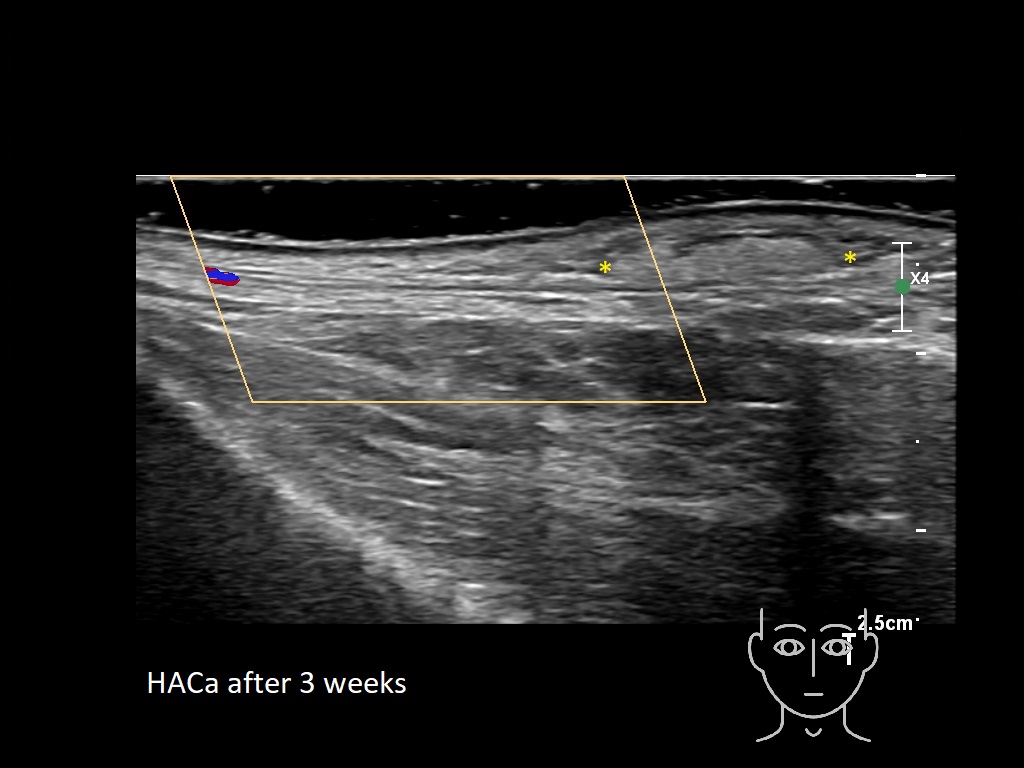

HAca11e